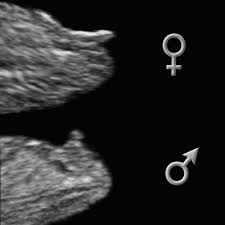

Placenta on left side of uterus = girl. The gender of the baby is determined at conception, althoug. Placenta on right side of uterus (also called the ramzi theory) = boy. Clinically proven to be 99.9% accurate We're not quite at the submit your order online and receive it within 30 minutes point. When you're looking at 50/50 odds, predictions are bound to come true half the time. Healthcare providers can do this test toward the end of the first trimester, usually at about 10. If you're curious to give it a try, here are the most popular ways moms claim you can tell a baby's gender from an early sonogram:

You will notice these after birth as well, during diaper changes. But developments in noninvasive prenatal tests (nipts) mean you can be let in on this little secret with a. Private parts nub point up more than 30. If you're curious to give it a try, here are the most popular ways moms claim you can tell a baby's gender from an early sonogram: If the line stops at your belly button, you're having a girl.

That dark line that runs from your pubic bone straight up the center of your belly (known as the linea nigra) is said to indicate baby's sex. Free baby gender prediction chart. Though expensive, you can have this test done through some companies that actually collect samples by post and let you know of your baby's gender in just a week. If you're curious to give it a try, here are the most popular ways moms claim you can tell a baby's gender from an early sonogram: How early you can tell the gender of your baby depends on the method of detection you use. But developments in noninvasive prenatal tests (nipts) mean you can be let in on this little secret with a. Placenta on right side of uterus (also called the ramzi theory) = boy. As these sound waves are released, they bounce off of internal surfaces and an image is generated on a computer monitor. Known as one of old wives tales, the chinese gender calendar is a very ancient tool allowing you to find out if the baby you're conceiving is a boy or a girl. Riesenauswahl an produkten rund ums baby. Can you tell gender at 10 weeks? Private parts nub point up more than 30. The gender of the baby is determined at conception, althoug.